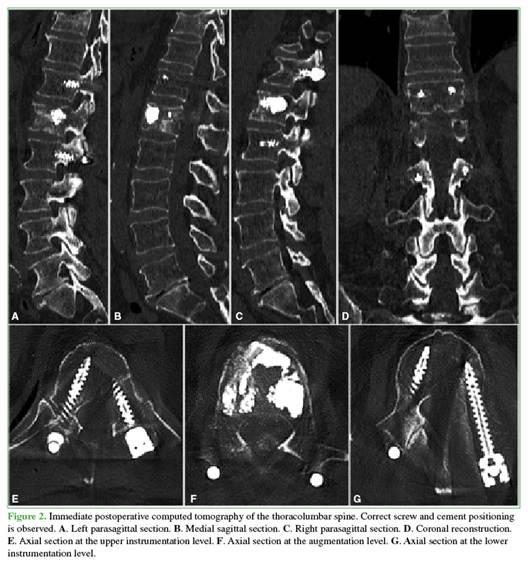

Postoperative images

Postoperative computed tomography confirmed correct pedicle screw placement and absence of intracanal cement leakage (Figure 2). No signs of spinal canal compression were observed.